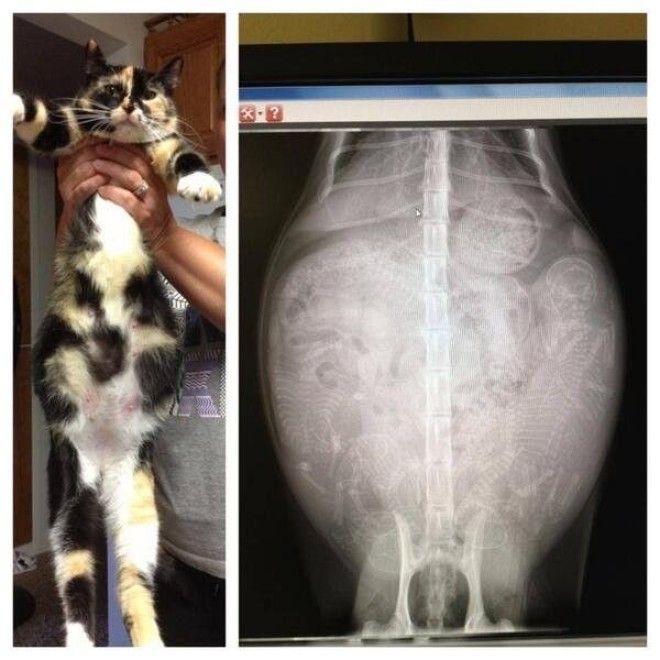

4. Еще одна кошка